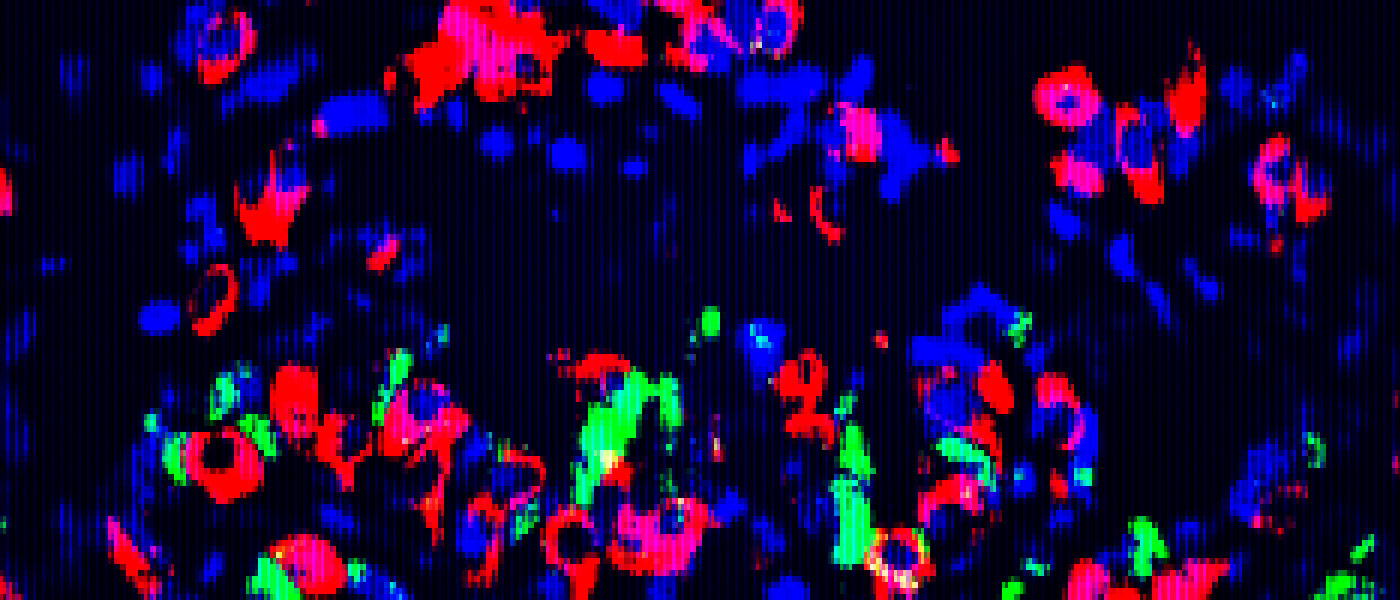

After their discovery, the researchers took samples of this specific tissue from mice in an effort to reprogram it into a beta-cell state. They then grew the tissues into “mini-organs” that successfully produced insulin when it was transplanted back.

The stem cells from the engineered organs also replenished the beta-cells, which means the tissue can sustainably regenerate.